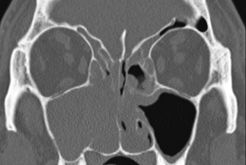

A 52year old male of Samoan descent presented to our centre in year 2003 with long term (>10years) nasal obstruction and clear nasal discharge. Anterior rhinoscopy showed bilateral grade IV nasal polyps. Nasoendoscopic examination of the left nasal cavity revealed numerous pale polypoid masses in the inferior meatus and middle meatus whilst the right nasal cavity was completely full of polyps. Computerized tomography (CT) scan revealed extensive bilateral disease with polyposis involving the paranasal sinuses, nasal cavity and nasopharynx. There was no evidence of bony sclerosis, thickening or destruction (Figure 1). He suffered from asthma and had undergone bilateral functional endoscopic sinus surgery (FESS) previously elsewhere. In 2004, with a preoperative diagnosis of chronic rhinosinusitis with bilateral polyposis, a revision FESS was preformed and the polyps were sent for histological examination. On macroscopic examination, the polyps from both sides appeared smooth, shiny and cream in colour. Histological examination of polypoid fragments from both sides was consistent with bilateral synchronous Shneiderian papilloma along with inflammatory polyposis.

Figure 1 Bilateral mucoperiosteal disease worse affecting the right nasal cavity (Year 2004).